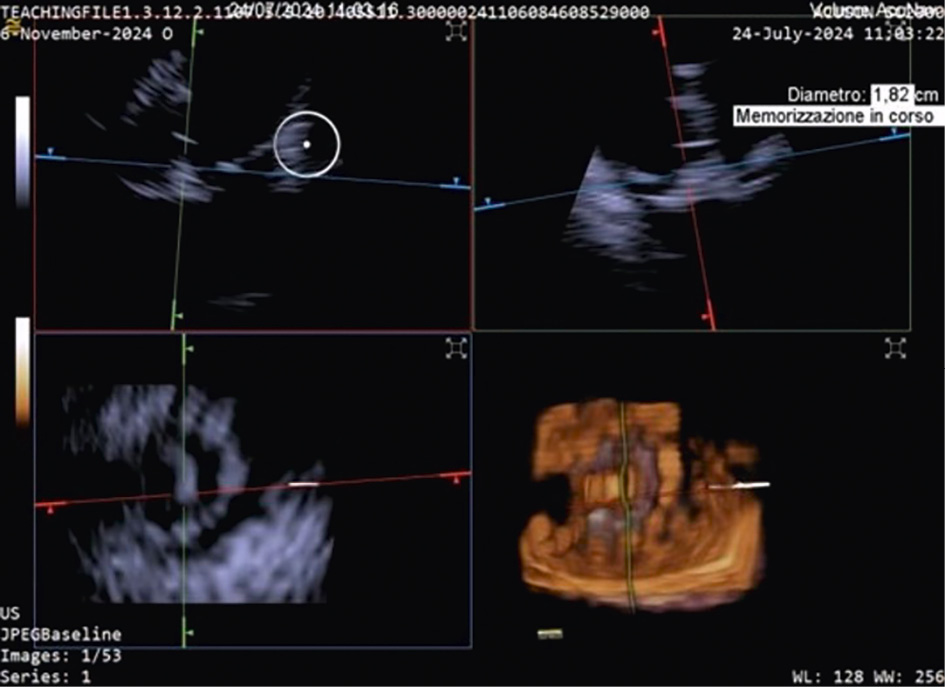

TTVR is a new technology used for tricuspid regurgitation (TR) treatment in patients not eligible for other percutaneous approaches23. The suitability for this treatment mainly depends on the annular dimensions, and unlike other treatment approaches, the imaging quality requirements are not very strict24. Three-dimensional ICE plays a crucial role in guiding the TTVR procedure, especially when TOE imaging is technically challenging. There are currently some cases described in the literature in which TTVR procedures are performed using combined 3D TOE-ICE imaging. Furthermore, there are only a limited number of centres with experience in ICE-guided TTVR24, but considering the advantages of image quality, it could become the standard in the coming years. Typically, the ICE probe is inserted via transfemoral or transjugular access and positioned in the middle of the RA. By placing the 3D ICE probe directly in the RA, the problem of acoustic interference can be overcome. Furthermore, this position allows for stable visualisation of the TV and enables the acquisition of a 3D MPR by placing the region of interest over the TV annulus, creating a 3D en face view. The leaflet capture and the valve implantation can be guided stepwise with 3D MPR25. A dedicated echocardiographer is essential to create and optimise the imaging modalities (TOE and ICE). In fact, considering that intraprocedural echocardiographic guidance is essential for procedural success, the interventional imager plays a crucial role in guiding the implantation of the device. Figure 5, Figure 6 and Moving image 8 show a Cardiovalve case (Venus Medtech) and a LuX-Valve case (Jenscare Scientific).

Figure 5. 3D MPR ICE imaging showing Cardiovalve device opening at the level of the tricuspid annulus. 3D: three-dimensional; ICE: intracardiac echocardiography; MPR: multiplanar reconstruction

Figure 6. Three-dimensional MPR views of the tricuspid valve after LuX-Valve deployment. The atrial en face view allows the evaluation of possible residual leakage. MPR: multiplanar reconstruction